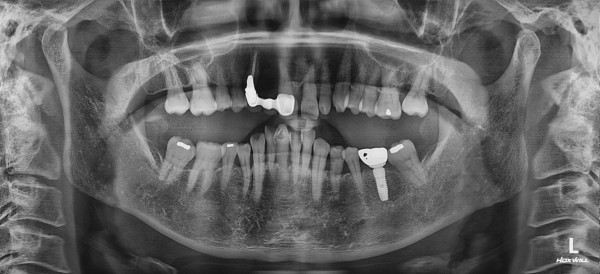

임플란트 재수술